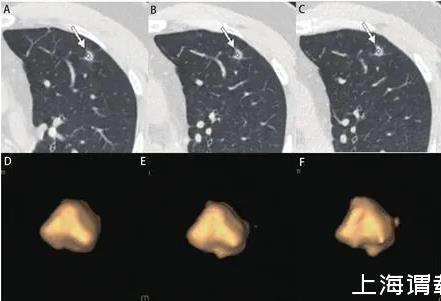

圖2男,47歲,左上葉實(shí)性結(jié)節(jié),直徑約為1.0 cm,病理為浸潤性腺癌。A、B:2013/03/12第一次CT檢查,體積為211 mm3;C、D:2013/10/10檢查,體積為235 mm3;E、F:2014/11/27檢查,體積為267 mm3。在20個(gè)月的隨訪中,結(jié)節(jié)體積無明顯增長,但術(shù)后病理診斷為腺癌。